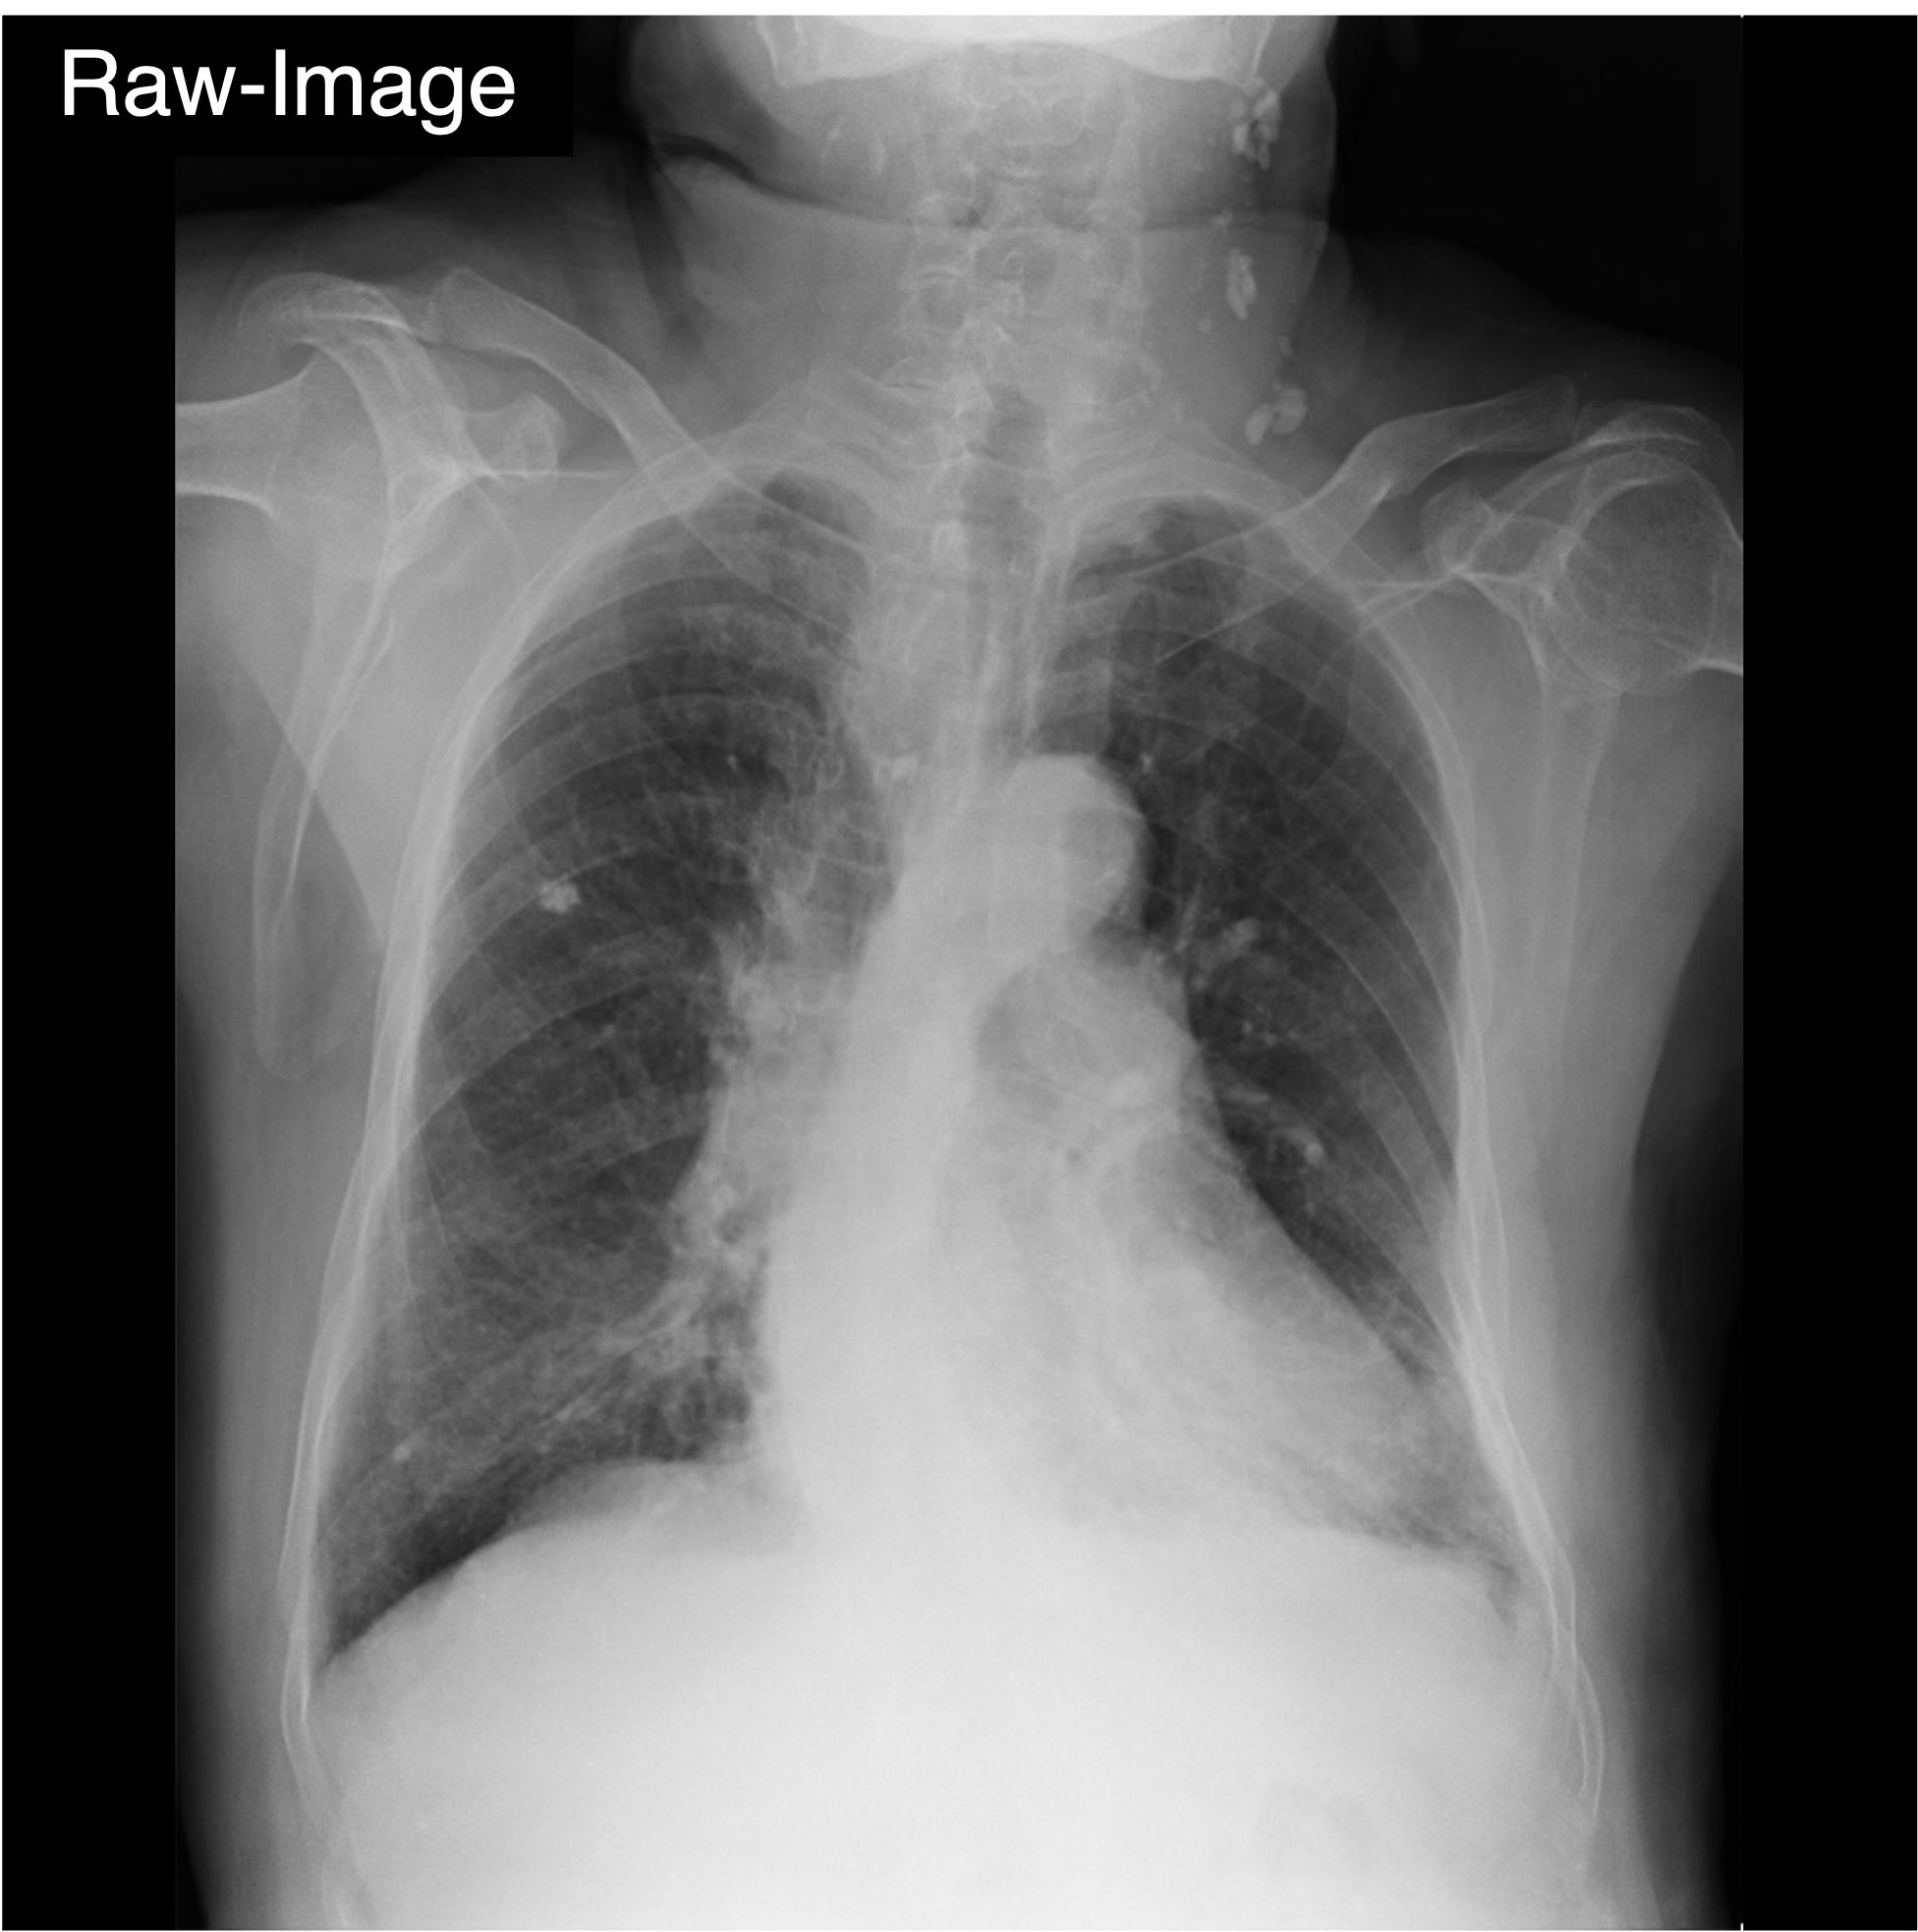

Qualitative Comparison. Comparison results between various state-of-the-art detection methods and the proposed method is shown above. Our method effectively leverages modality context to significantly enhance anomaly localization (red), compared to baseline results (blue). Ground truth bounding boxes are green. For cases where the bounding boxes are small, insets show an enlarged view of the highlighted yellow region.